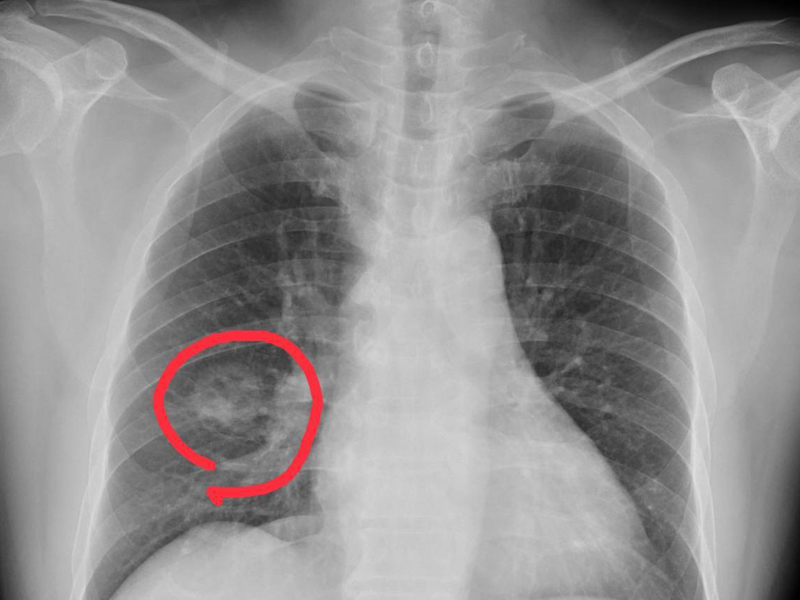

肺癌來臨並非無聲無息,提醒:手腳出現 4 種異常,可能是肺癌到來,不要大意!

一般情況下手指變粗很可能是肺癌的信號,尤其是長期吸煙的男性朋友,要特別警惕杵狀指,也就是手指末端變粗,增生,膨大,同時還會伴有咳血、刺激性乾咳、胸痛等症狀。